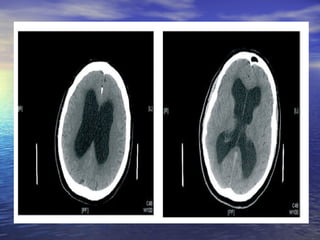

Hidrocefalia normotensiva.Hidrocefalia normotensiva.

INDICE DE EVANS >0,3.INDICE DE EVANS >0,3.

INDICE DE EVANS>0,3.INDICE DE EVANS >0,3.